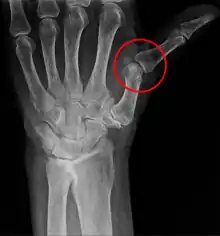

فرسودگی در پزشکی، افتادگی دررفتگی ناقص یا جزئی مفصل یا اندام است.[1] طبق سازمان جهانی بهداشت (WHO)، ساب لکسانس «جابجایی ساختاری قابل توجهی» است، بنابراین در مطالعات تصویربرداری ساکن، مانند اشعه X، همیشه قابل مشاهده است. این در تضاد مستقیم با باور کایروپراکتیک «فرو رفتگی مهرهها» است.[2]

سابلاکساسیون مفصل جایی است که استخوان متصل بهطور جزئی از مفصل خارج شود.[3] برعکس یک حالت تجمعی، یعنی جداسازی کامل مفاصل، یک فرو رفتگی اغلب بدون کمک اضافی از یک متخصص بهداشت و درمان حرفهای به حالت طبیعی خود برمی گردد.[4] به عنوان مثال زیر مفصل مفصل، آرنج یک پرستار خانم است که به حالت زند زبرین رباط حلقوی است. مفاصل دیگری که مستعد گرفتگی زیر ران هستند، شانهها، انگشتان، مچ دستان، دندهها، مچها، کشکک، مچ پا و لگن است که تحت تأثیر دیسپلازی مفصل ران قرار دارند. گرفتگی نخاع در اشعه ایکس قابل مشاهده است و گاهی اوقات میتواند به ریشههای عصب نخاعی برخورد کند و باعث ایجاد علائمی در نواحی ارائه شده توسط آن ریشهها شود. در ستون فقرات، چنین جابجایی ممکن است به دلیل شکستگی، اسپوندیلولیستیز، آرتریت روماتوئید،[5] آرتروز شدید، سقوط، تصادفات و آسیبهای دیگر ایجاد شود. این در نشانگان اهلرز-دنلوس شایع است.